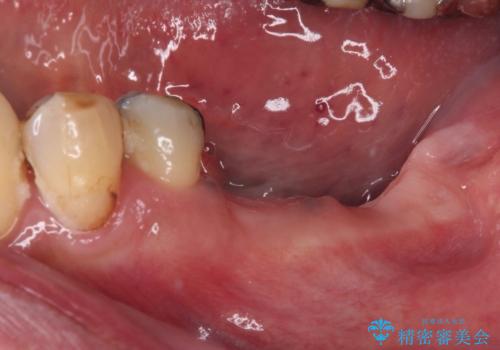

- 抜歯をしたものの、インプラントにするか入れ歯にするか悩んでいるうちに2年以上経過してしまったとのことで来院された患者様です。

インプラントにはストローマン社のSLActiveを使用し、埋入から補綴までおよそ3か月と、短期間で治療を進めることができました。